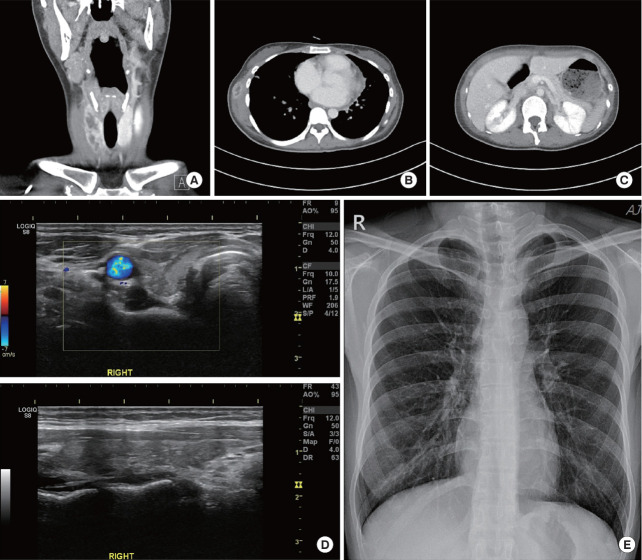

Abstract Image